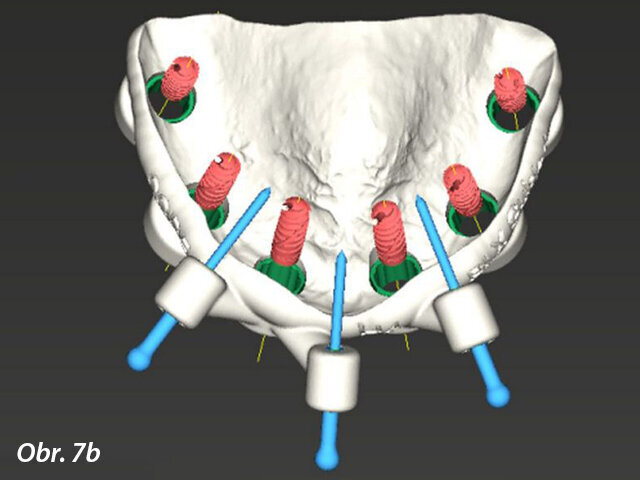

Prostřednictvím softwaru coDiagnostiX jsme zjistili, že je k dispozici dostatek kosti pro zavedení implantátů, kromě dvou oblastí, do nichž bude nutno transplantovat kostní štěp (obr. 5, 6). Bylo naplánováno celkem šest implantátů s adekvátním rozložením po oblouku, které vytvoří podpěru pro žvýkací síly a zabrání jednostranné zátěži (obr. 7). Zavedení implantátů bylo naplánováno za použití chirurgické šablony (obr. 8) a na implantáty měla být hned po chirurgickém zákroku našroubována provizorní náhrada – jednalo se tedy o protokol okamžitého zatížení.